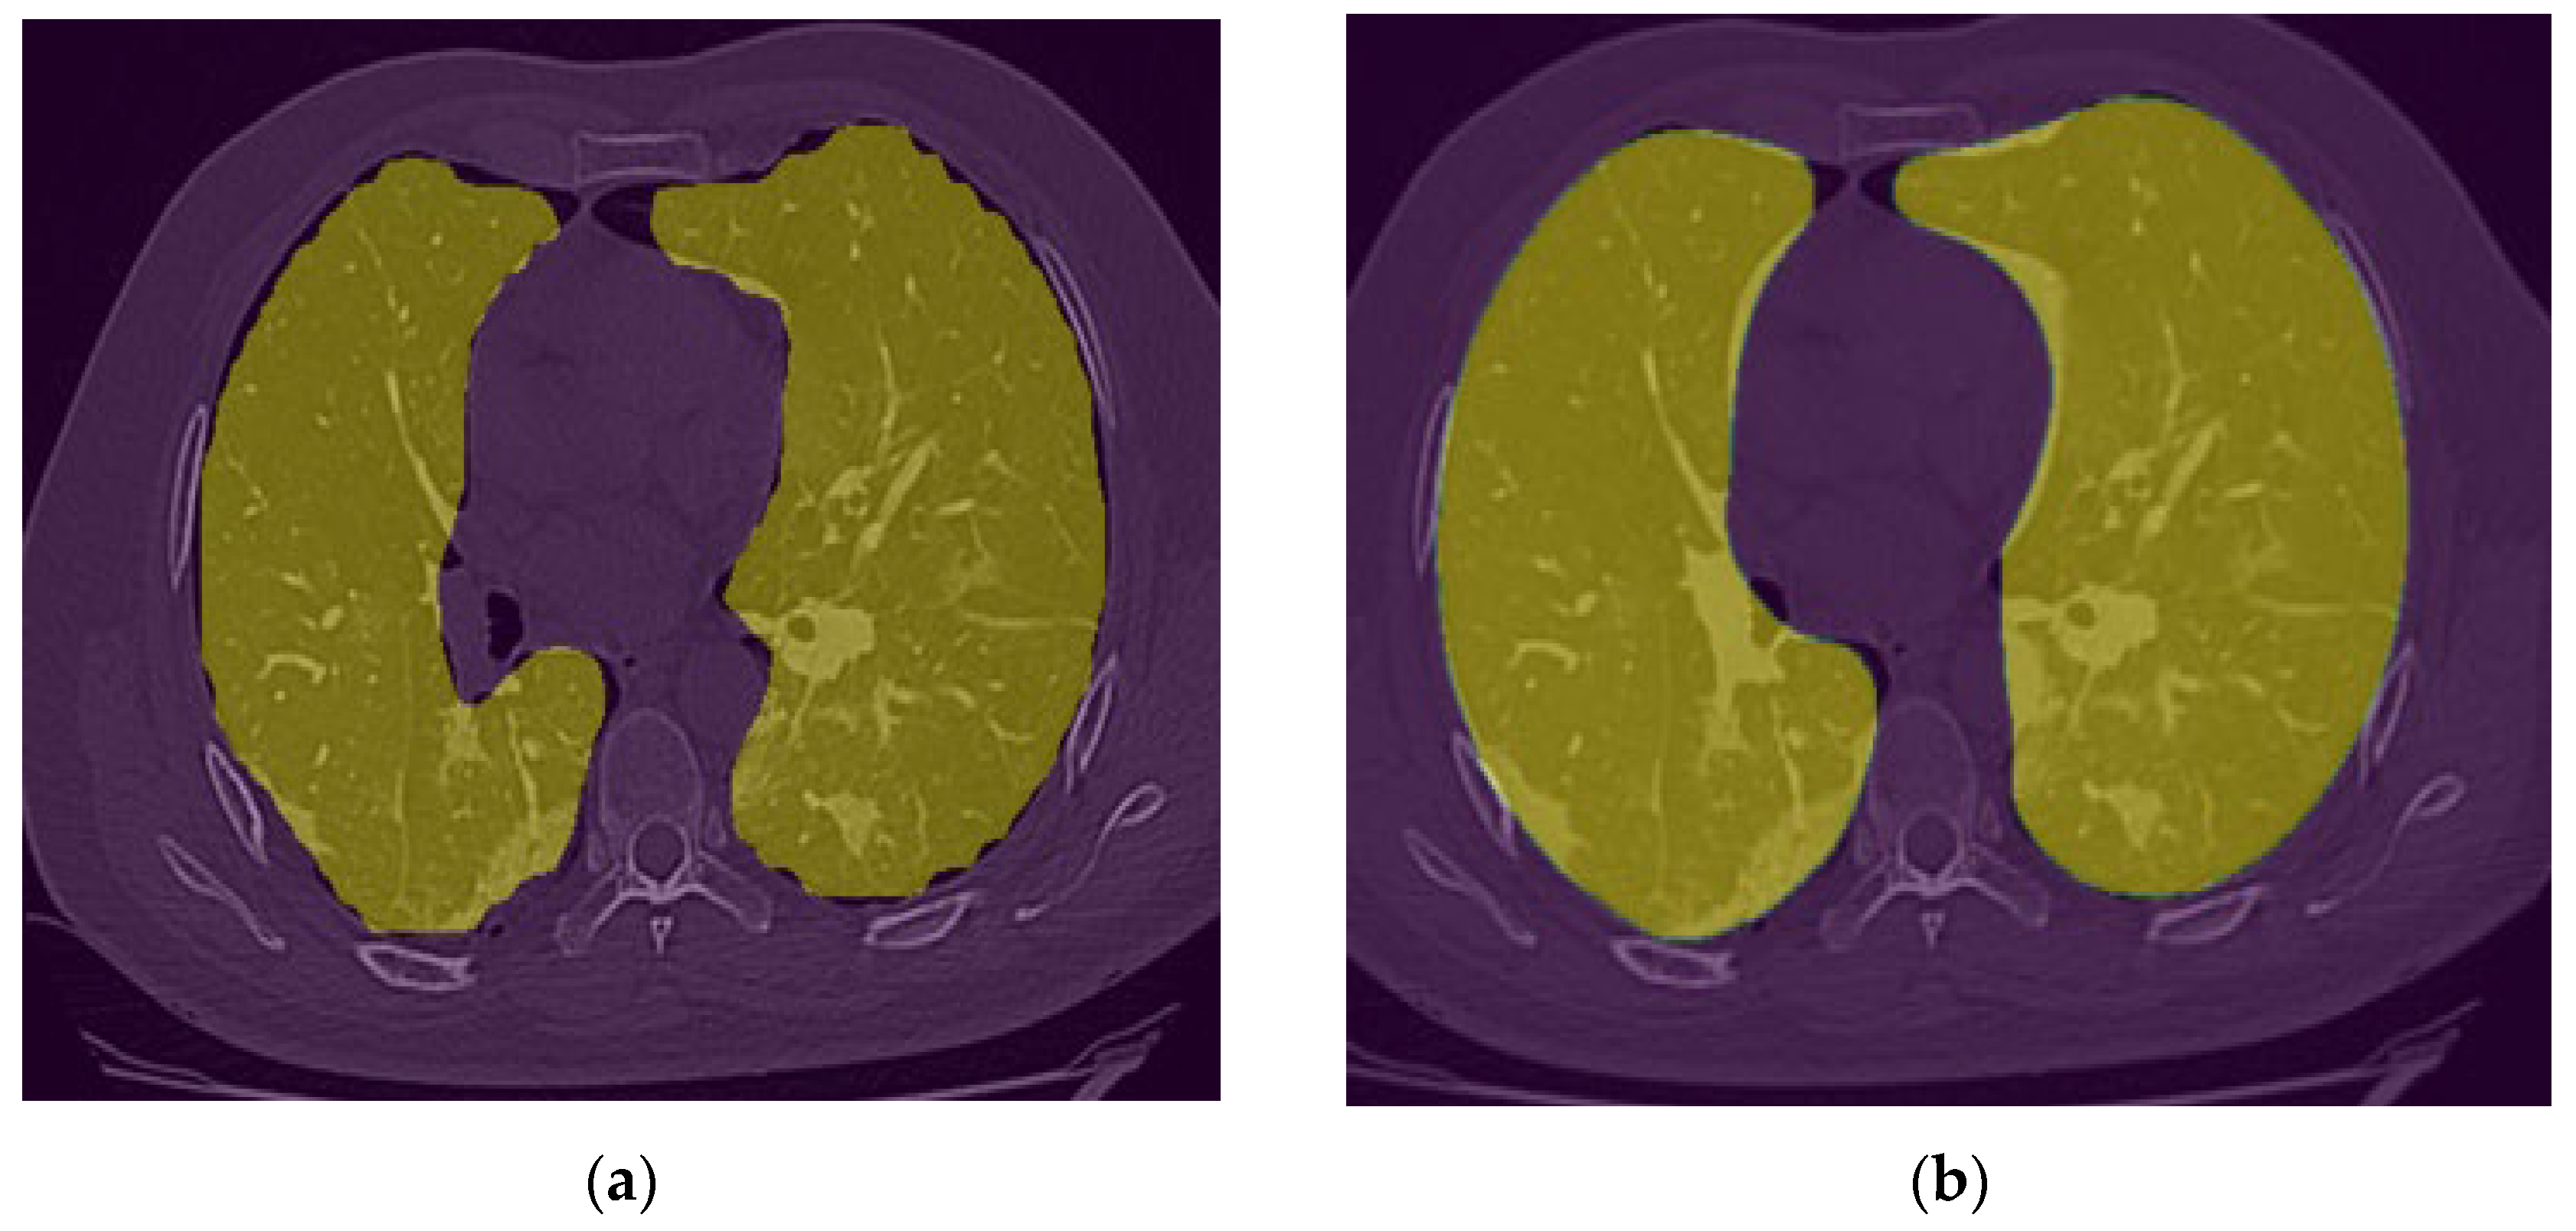

2.4. Image preprocessing

After observing the output of the lung segmentation model, it was noted that in several cases with sever disease infection, small percentage of the lung may be missing from the segmentation as shown in Figure 5-a, which are typically represent disease infection area. In order to include or recover the missed lung area if the lung segmentation error is visually observed from our GUI, the user (i.e., radiologist) can call an image a specially-designed post-processing function that applies a unique conventional image processing algorithm inspired by the rolling ball algorithm [24] to automatically correct segmentation error. This algorithm starts with extracting the lung contours followed by several steps and morphological filters such as disk drawing, filling holes, median, and erosion operations. As shown in Figure 6, it can convert a jagged and rough lung boundary as shown in Figure 6-a to a smooth one which covers the previously missed lung area as shown in Figure 6-b. While it might lead to a small over-segmentation in some cases, the previously missed area contains very important infected lesions that can significantly affect the assessment of sever cases.

Figure 6. (a) lung segmentation mask (b) post-processing lung segmentation.